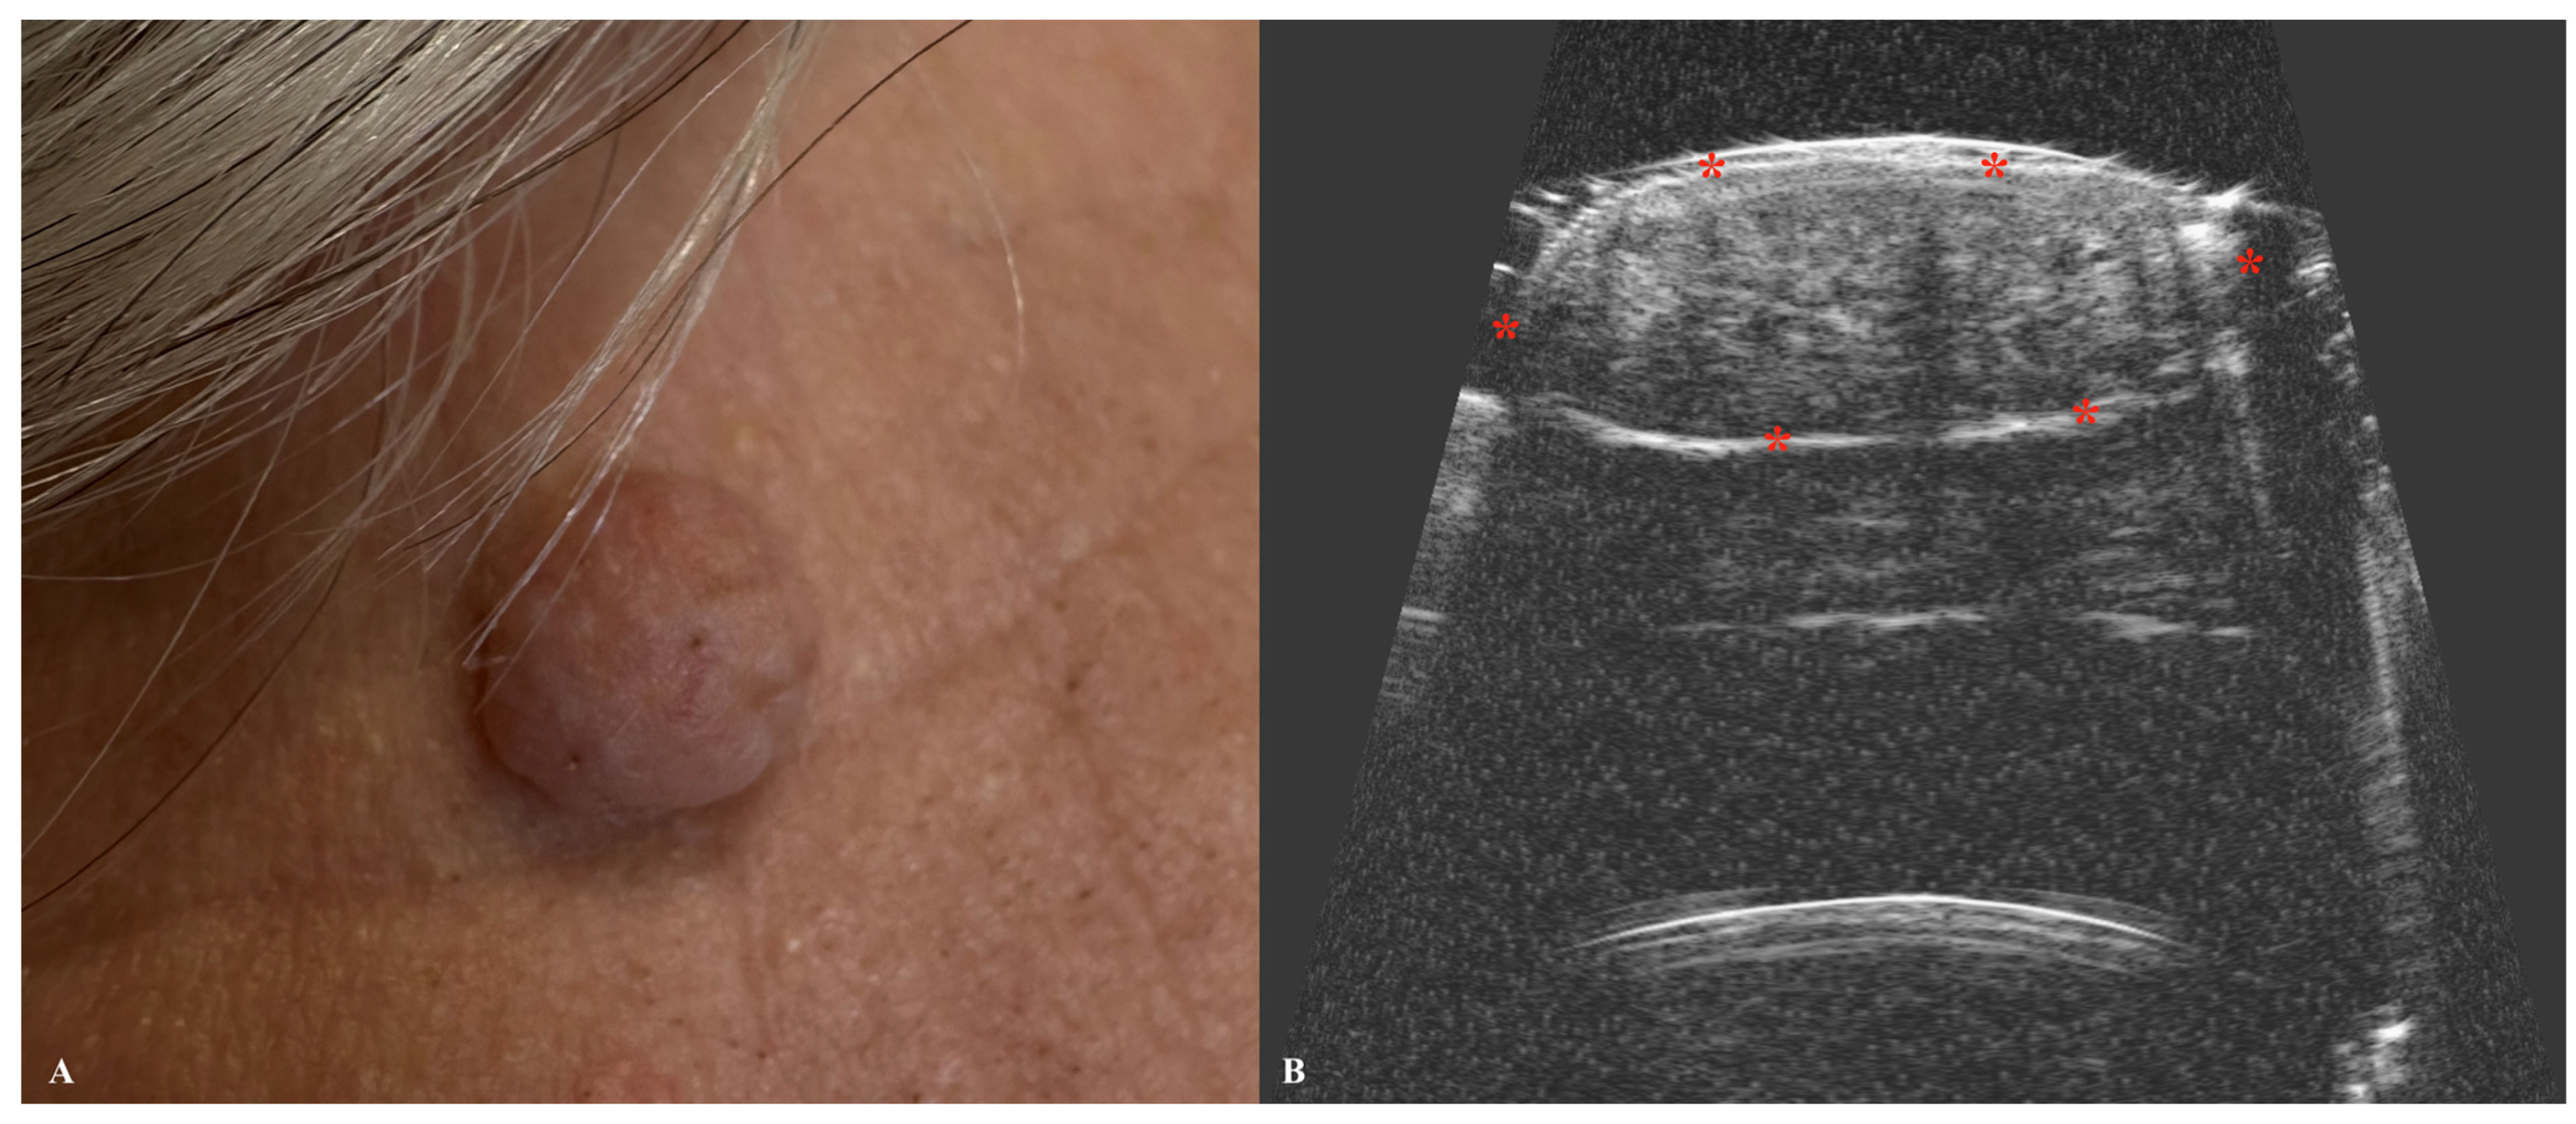

5. Melanoma

| Melanoma | Hypoechoic, heterogeneous lesion with an oblong or oval shape. Often well demarcated by a hyperechoic epidermal layer. Hypervascular on Doppler. |